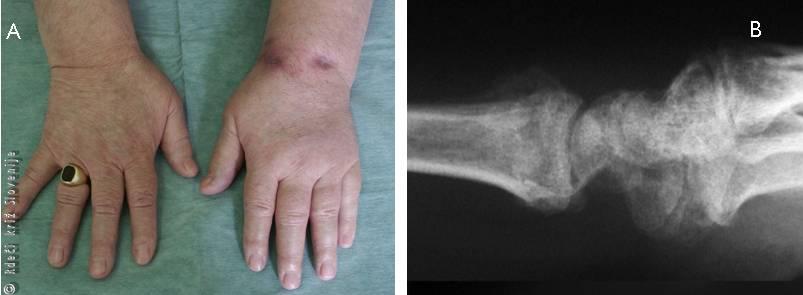

Primer 1

12-letna deklica se je na prigovarjanje vrstnikov s kotalkami spustila vzvratno po cesti navzdol. Ob tem je zgubila ravnotežje, padla in se ujela na iztegnjeno dlan. Zaščitne opreme ni imela. Roka jo je pričela zelo boleti in pojavila se je naraščajoča oteklina. Gibaje v zapestju je bilo zaradi bolečine povsem zavrto. Deklica si je roko vseskozi podpirala z nepoškodovano roko. Vrstniki so jo pospremili domov, kjer ji je mama namestila ruto in oteklo mesto hladila z brisačo namočeno v hladno vodo. Ker se je bolečina stopnjevala jo je odpeljala v urgentno službo bližnje bolnišnice. Po pregledu in rentgenskem slikanju so ugotovili, da ima zlom koželjnice na značilnem mestu. Napravili so uravnavo zloma v splošni anesteziji. Deklica je dobila doramenski mavec. Nato so oskrbeli še rane na obeh kolenih.

Slika 8

A – Nepravilna oblika zapestja.

B – RTG znaki zloma koželjnice na značilnem mestu.